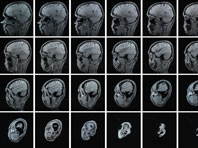

Кардиологи обратились к трехмерным технологиям, чтобы повысить точность операций, передает Reuters. Они прооперировали пациента в специальных очках, которые позволяют видеть то, что происходит в грудной клетке пациента в трех измерениях. Хирургам уже известны системы, собирающие во время операции информацию о теле человека, но они представляют данные в виде двухмерных изображений на обычном мониторе. Такие изображения…